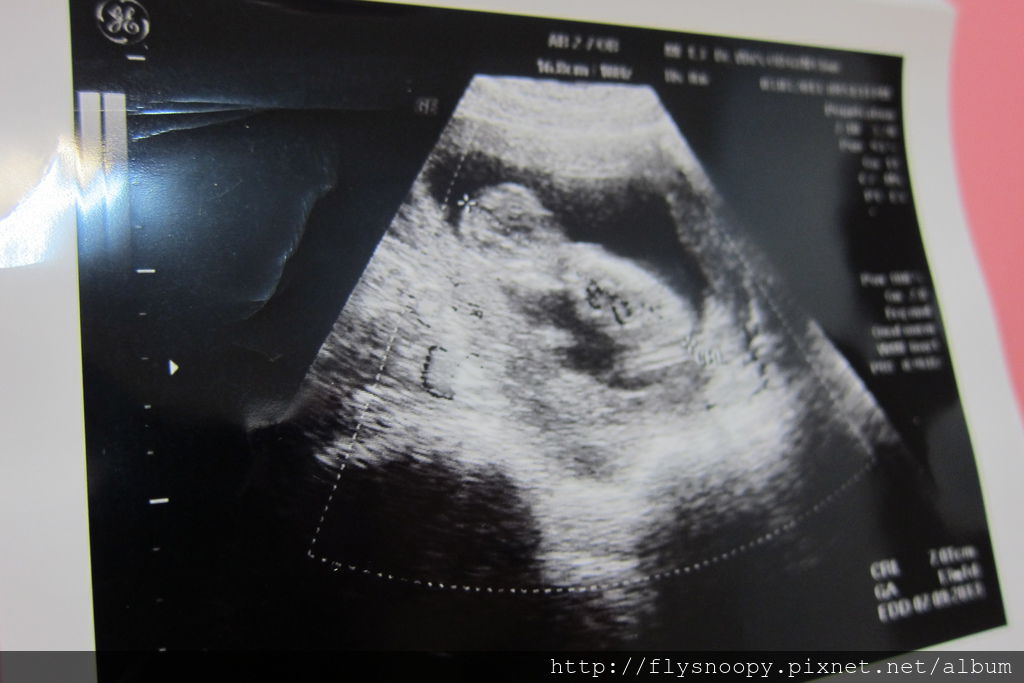

BPD(胎兒頭骨橫徑):9cm

EFW(預估體重):108g

現在可以很清楚看見baby的手腳,baby正在玩自己的手耶

4D的照片還不是很好看

醫生說baby大一點會更漂亮喔,期待

這次產檢因為baby躺著,角度的關係所以還不知道性別